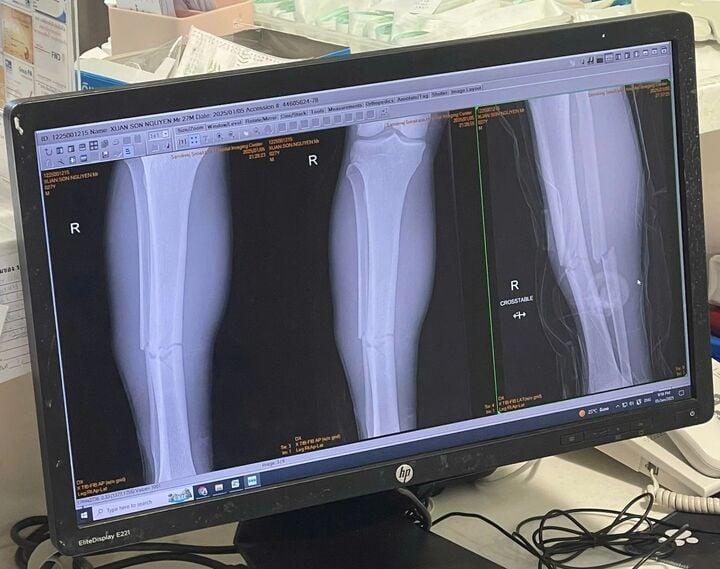

Phim chụp vết xương gãy của Xuân Son.

Theo thông tin của Báo điện tử VTC News từ Thái Lan, Nguyễn Xuân Son bị gãy 2 xương vùng ống chân (xương chày và xương mác). Cầu thủ sinh năm 1997 phải điều trị bằng phẫu thuật để cố định xương, chắc chắn mất nhiều tháng để hồi phục.